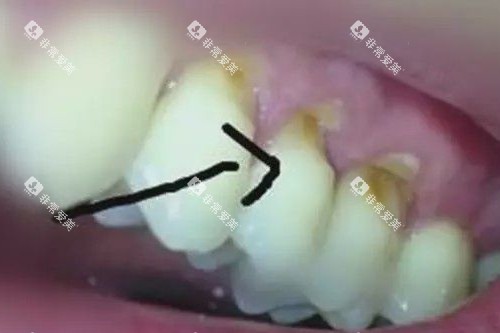

楔状缺损的罪魁祸首,正是90%人都在用的错误刷牙方式:

暴力横刷:牙刷毛硬、用力过猛,牙颈部釉质被“磨”出V型缺口